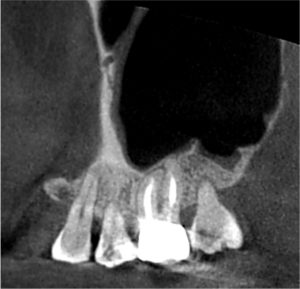

矯正の先生からは、内部吸収をしているので治してほしいと言われてたのですが、レントゲンを撮って良く見てみるとこれは外部吸収でした。

内部吸収というのは、歯の内部が溶けてしまう病気で虫歯とは違います。

外部吸収も同様に虫歯ではなく、破歯細胞が歯の外側から歯を溶かしていき歯の内部に吸収が侵攻する病気です。

上のレントゲンを見ていただくとわかると思いますが、赤矢印の先(歯の外側から)吸収が開始され、歯の内部に吸収が向かい黄色矢印のところまで歯の内部が溶けてしまっているのです。

この病名は、ICR(Invasive Cervical Resorption)「侵襲性歯頸部外部吸収」(しんしゅうせいしけいぶがいぶきゅうしゅう)といいまして、